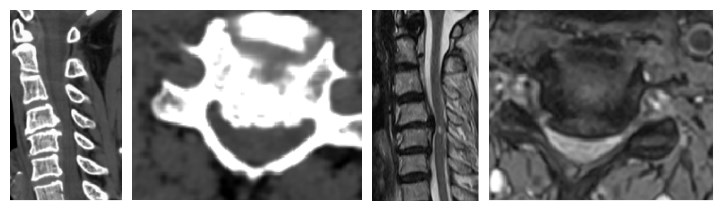

患者經(jīng)頸椎CT/MRI檢查后,提示有:頸椎反弓,頸4/5椎間盤突出,后縱韌帶骨化,頸4/5層面椎管明顯狹窄,相應(yīng)脊髓變性。

頸椎CT/MRI